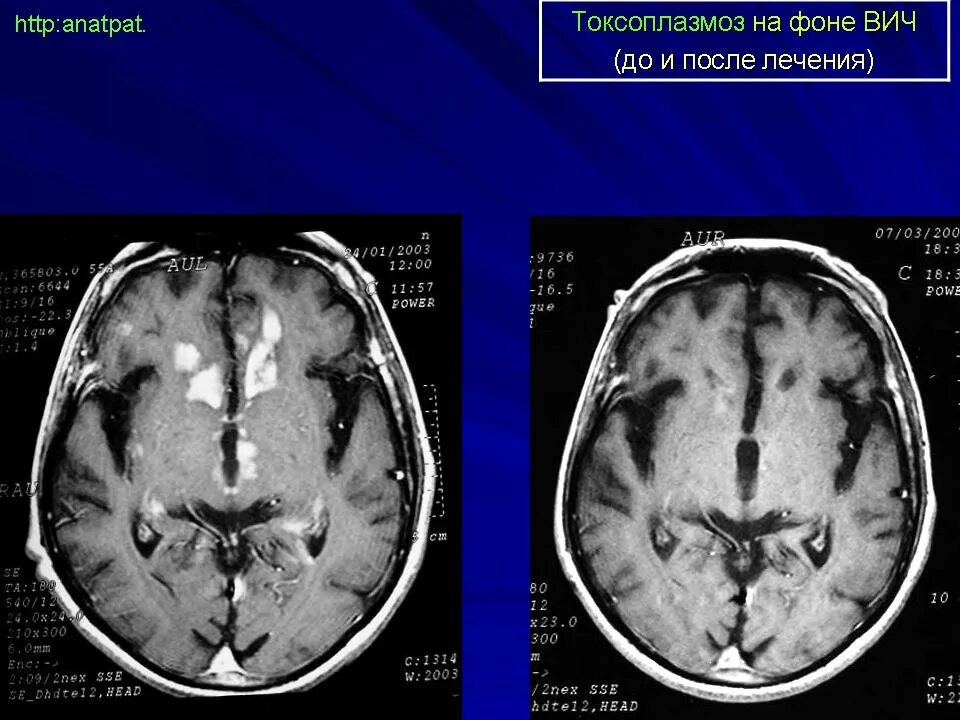

Токсоплазмоз у вич инфицированных